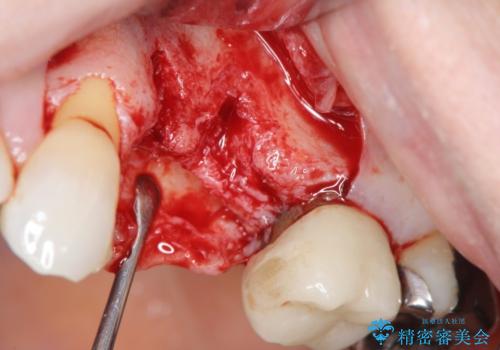

抜去後の補綴治療は長いブリッジではなくインプラント治療を希望されましたが、穿孔・破折による周囲の骨吸収をリカバリーすべく骨の造成を伴うインプラント治療を計画します。

インプラント治療を行うにはインプラント周囲に十分な骨の幅・高さが必要です。

今回はが原因で失われてしまった骨の幅を回復することで長期的な予後を見込めるインプラント治療を行うことができました。